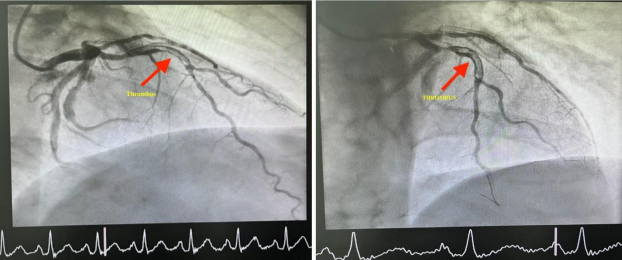

Coronary angiography showed a large caliber ectatic left anterior descending (LAD) artery, which was occluded by thrombus (Figure 1). Despite difficulties in wiring the LAD, the involved segment was successfully ballooned in an escalated fashion, restoring TIMI-3 flow. An ectatic segment that is just distal to the involved segment was also noted, which was studded with thrombus, resulting in a very hazy picture (Figure 2). Although attempts were made to aspirate the thrombus using an Export catheter (Medtronic, MN, USA), it was unsuccessful. Since the patient was symptomatically and hemodynamically stable, a decision was then made to medically manage him for the next 24-48 hours before attempting the procedure again.

Figure 1: Diagnostic angiogram showing a complete occlusion of LAD.

Figure 2. Baseline Coronary Angiography showing large thrombotic lesion in the LAD (arrows)